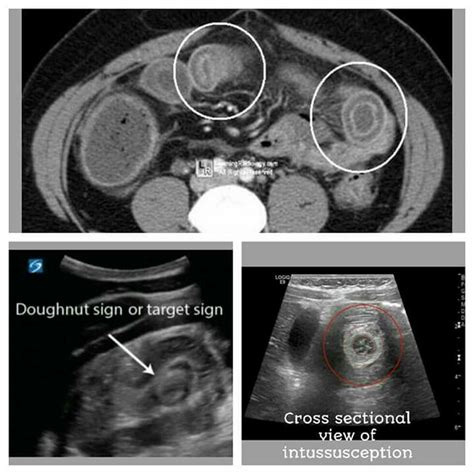

Web the target sign of intestinal intussusception, also known as the doughnut sign or bull's eye sign. This indicates mesenteric fat around the head of the intussusception. See target sign of intussusception; The appearance is generated by concentric alternating echogenic and hypoechoic bands. Gastric adenocarcinoma with central ulceration Earliest lesion seen in crohn disease gastric lymphoma with central ulceration 4; Web target sign (also known as the doughnut sign) pseudokidney sign. Crescent in a doughnut sign. Web the doughnut sign or target sign refers to the alternating echogenic (mucosa and muscularis)) and hypoechoic (submucosa) concentric bands which are caused by the invagination of the bowel if you look carefully at this clip you can see the classic “doughnut” or target sign of intussusception. Web unfortunately, the circular mass may be strikingly similar to the “target sign” or “donut sign” seen in intussusception due to concentric layers of echogenic bowel.

Web the target sign, as the presented case, consists of a round soft tissue mass that contains a radiolucent ring of fat within the intussusception. Earliest lesion seen in crohn disease gastric lymphoma with central ulceration 4; Web the target sign of intestinal intussusception, also known as the doughnut sign or bull's eye sign. The appearance is generated by concentric alternating echogenic and hypoechoic bands. Web unfortunately, the circular mass may be strikingly similar to the “target sign” or “donut sign” seen in intussusception due to concentric layers of echogenic bowel. Web the doughnut sign or target sign refers to the alternating echogenic (mucosa and muscularis)) and hypoechoic (submucosa) concentric bands which are caused by the invagination of the bowel if you look carefully at this clip you can see the classic “doughnut” or target sign of intussusception. Gastric adenocarcinoma with central ulceration Features that favor ileocolic over small bowel intussusception 14: Web the target sign, as the presented case, consists of a round soft tissue mass that contains a radiolucent ring of fat within the intussusception. This indicates mesenteric fat around the head of the intussusception. Web there are many bull's eye signs, many also called target signs: